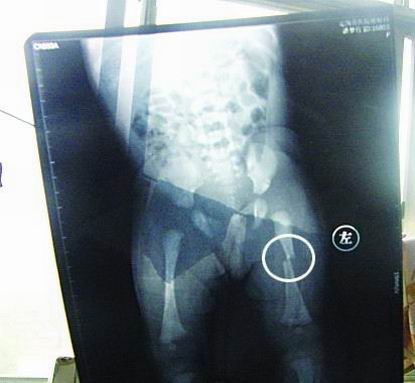

CT顯示小夢(mèng)竹左下肢骨折

今年7月2日下午,定陶縣南王店鄉(xiāng)沈莊村孕婦聶元真,在定陶縣人民醫(yī)院剖腹產(chǎn)下一女嬰,取名為潘夢(mèng)竹。醫(yī)院說,嬰兒出生后窒息,診斷為新生兒缺血缺氧性腦病,頭皮血腫。當(dāng)晚發(fā)現(xiàn)女嬰左下肢部位異常,第二天拍片顯示為左下肢骨干骨折。7月3日,潘夢(mèng)竹的頭顱CT顯示其頭頂部骨折,蛛網(wǎng)膜下腔出血,顱內(nèi)血腫。